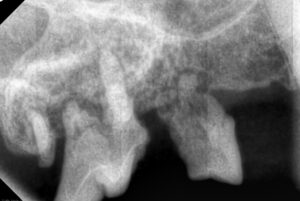

全身麻酔下で歯科レントゲンと歯周ポケットの測定(プロービング)などを行います。

これらの検査により、表面からは見えない顎の骨や歯根の状態を把握できます。

今回の歯科レントゲンでは、歯を支える顎の骨(歯槽骨)が重度に失われ歯根の周囲が露出している状態でした。

この状態になると歯垢・歯石を取り除くだけでは改善が難しく、ご家族と相談の上で抜歯を主体とした治療を行うこととなりました。